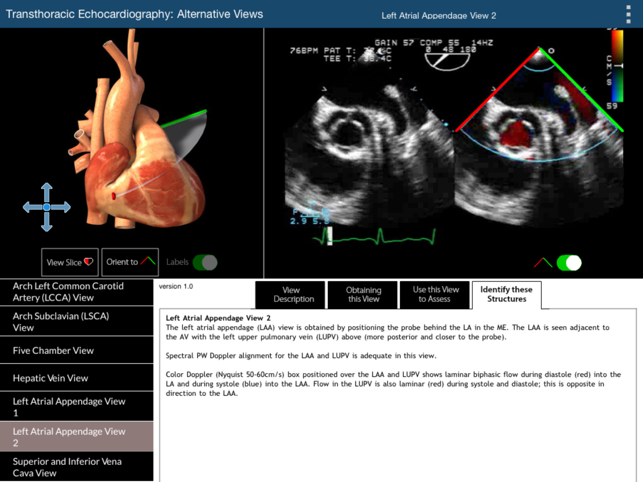

The primary challenge in learning TEE is translating the two dimensional echocardiographic image into a visualization of the complex three-dimensional (3D) structure of the heart. This TEE Alternative Views app provides a learning environment where users can explore 19 non-standard but complimentary 2D TEE views using two visualization methods simultaneously: (1) a rotatable 3D heart model with an echocardiographic plane and (2) the associated TEE clip. The 3D heart model and echo plane can be rotated, helping to relate the echocardiographic image to heart structures. Part of the heart above the echo plane can be removed, revealing the internal cardiac structures that correspond to the TEE image. This app will enable the user to perform a more complete TEE study than can be obtained from the 20 standard TEE views. For the 20 standard TEE views, please refer to our TEE Standard Views app. The 19 alternative TEE views illustrated in this app are: Coronary Sinus View (100 Degrees) Cor